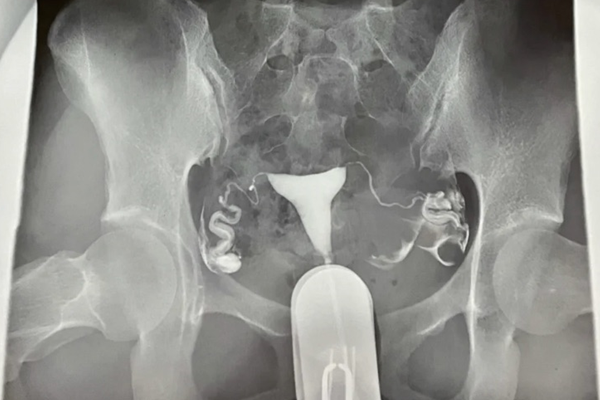

真相鉴定:“医生不建议做输卵管造影”是谣言,输卵管造影检查是通过导管向子宫腔及输卵管注入造影剂,利用X线诊断仪或者B超行透视及摄片,根据造影剂在输卵管及盆腔内的显影情况来了解输卵管是否通畅、阻塞部位及子宫腔形态的一种检查方法。特别是对于不孕不育的女性就需要进行检查。

造影是不能把输卵管通开的。子宫的输卵管造影,只是一个检查,而不是一个治疗手段。子宫输卵管造影是将碘剂直接由子宫颈管注入子宫腔,在经子宫腔到输卵管,在X线透视下,了解子宫腔和输卵管的通畅性。